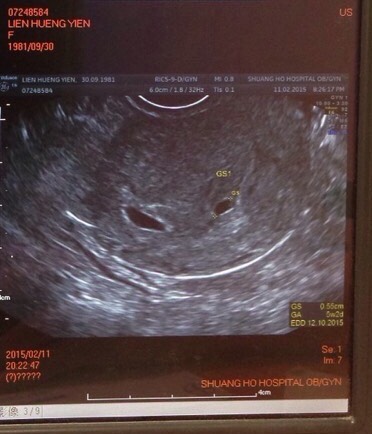

超音波顯示,左大右小,疑似是兩個北鼻喔!!

右邊的可能是,又可能不是喔

左邊的大北鼻是0.88cm,右邊的小北鼻是0.55cm

約5w多

我也搞不清楚有沒有卵黃囊之類的東西,醫生啥都沒說嘛!